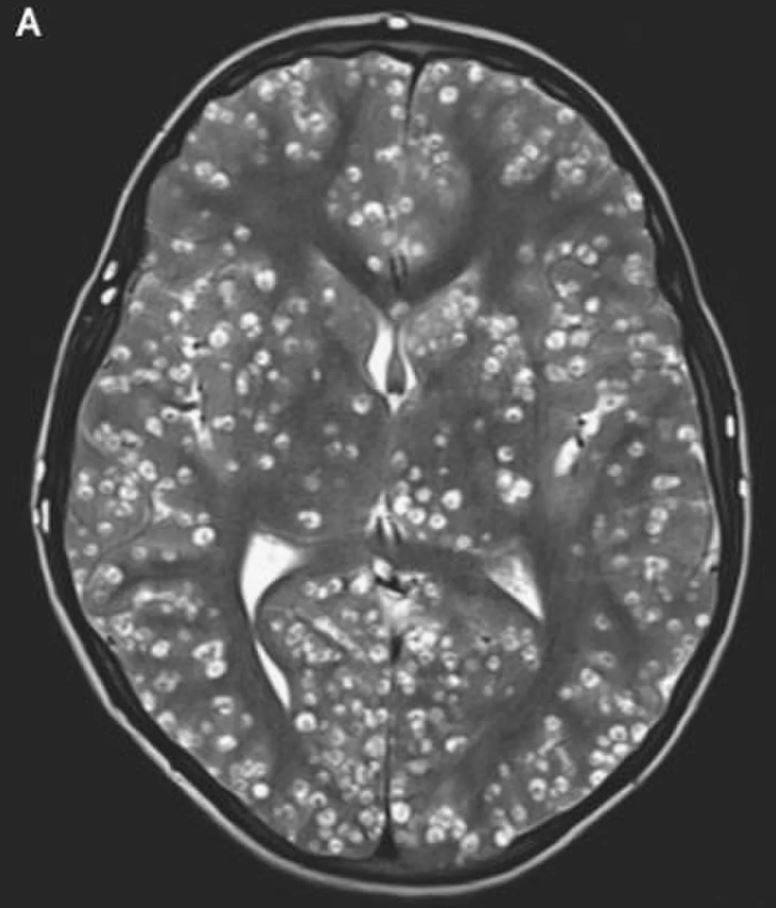

That’s when an MRI revealed cerebral cortex and brain-stem damage caused by cysts. He was diagnosed with neurocysticercosis, which is caused by ingesting tapeworm eggs that have passed in the feces of someone with an intestinal tapeworm.

The larvae wiggle out of their eggs and find a home in muscle and brain tissues, where they form cysts. They were also discovered in the patient’s right testicle and eye.